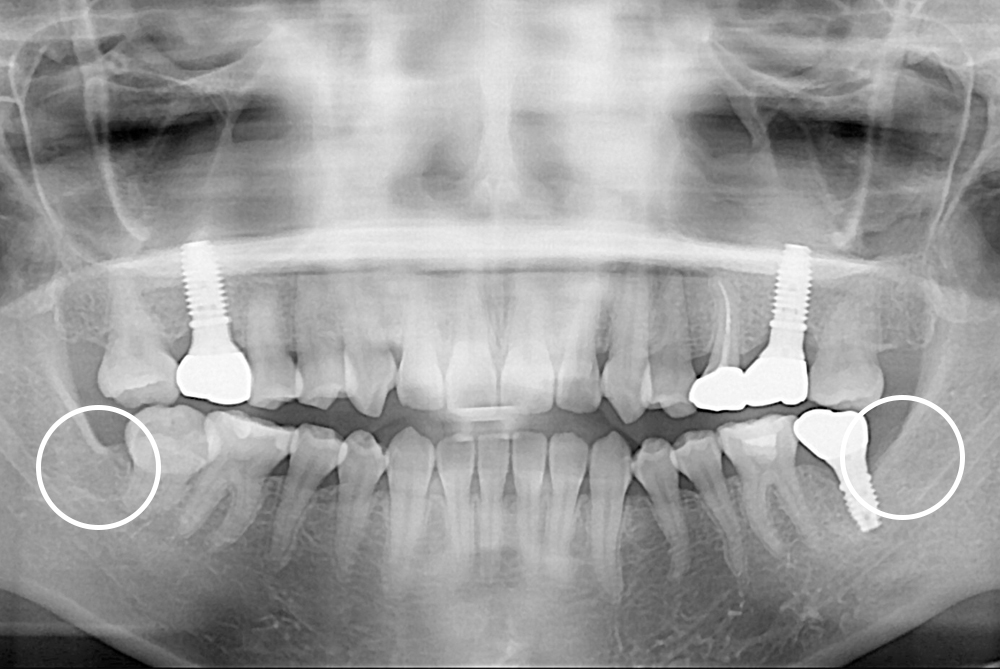

[사랑니] 매복 사랑니 발치

치료후 : 2019-09-25

세종치과는 구강악안면외과학 박사이신 원장님이 발치하는 치과입니다.